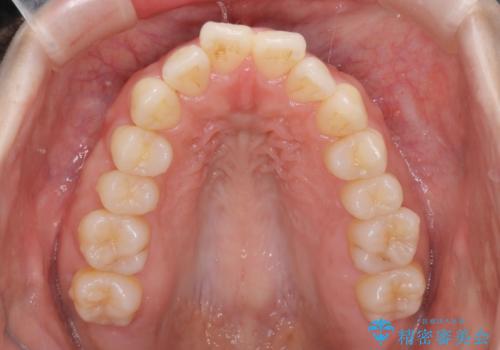

- 前歯の前突を主訴に来院されました。

下の前歯は癒合歯がある珍しいケースです。

治療に関しては小臼歯を4本抜歯して前歯を下げるような計画を立てて治療しました。

抜歯スペースの移動量を調整するために、矯正用アンカースクリューや親知らずを活用して治療を行いました。